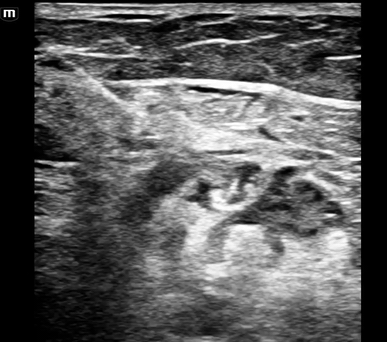

• This patient’s anatomy was not as clear as the above example images, but below are the clips from this case.

• The sciatic nerve at the split into the CPN and TN is seen just above and slightly to the right of the popliteal vessels